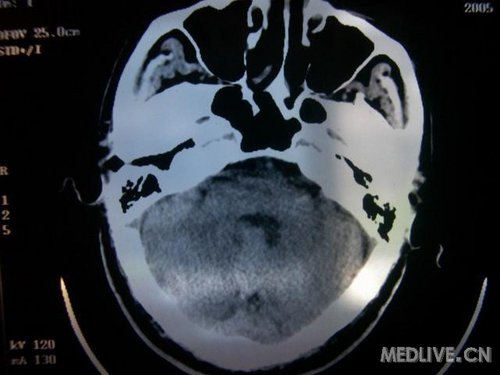

病人男性 73岁 市民 以“幻听、幻视两天,言语含糊、精神错乱一天”入院。

两天前无诱因出现幻听、幻视,描素眼前有彩色的圆圈,听见有人说话(但说什么不详),一天前出现胡言乱语,言语含糊,精神错乱,问话不答,行走略有不稳,来我院就诊,门诊头CT检查:(下面有片)入院后查体不合作,表情淡漠,问话不答,大致检查了一下,颅神经未见明显异常,颈软,右手活动似忽略差。其他检查不配合。脑电图:广泛轻-中度异常。

既往史:半年前曾患“右侧脑梗塞”但无明显后遗症,生活能自理,无高血压、糖尿病、心脏病史。

先传半年前的片子:

此次入院时的片子: